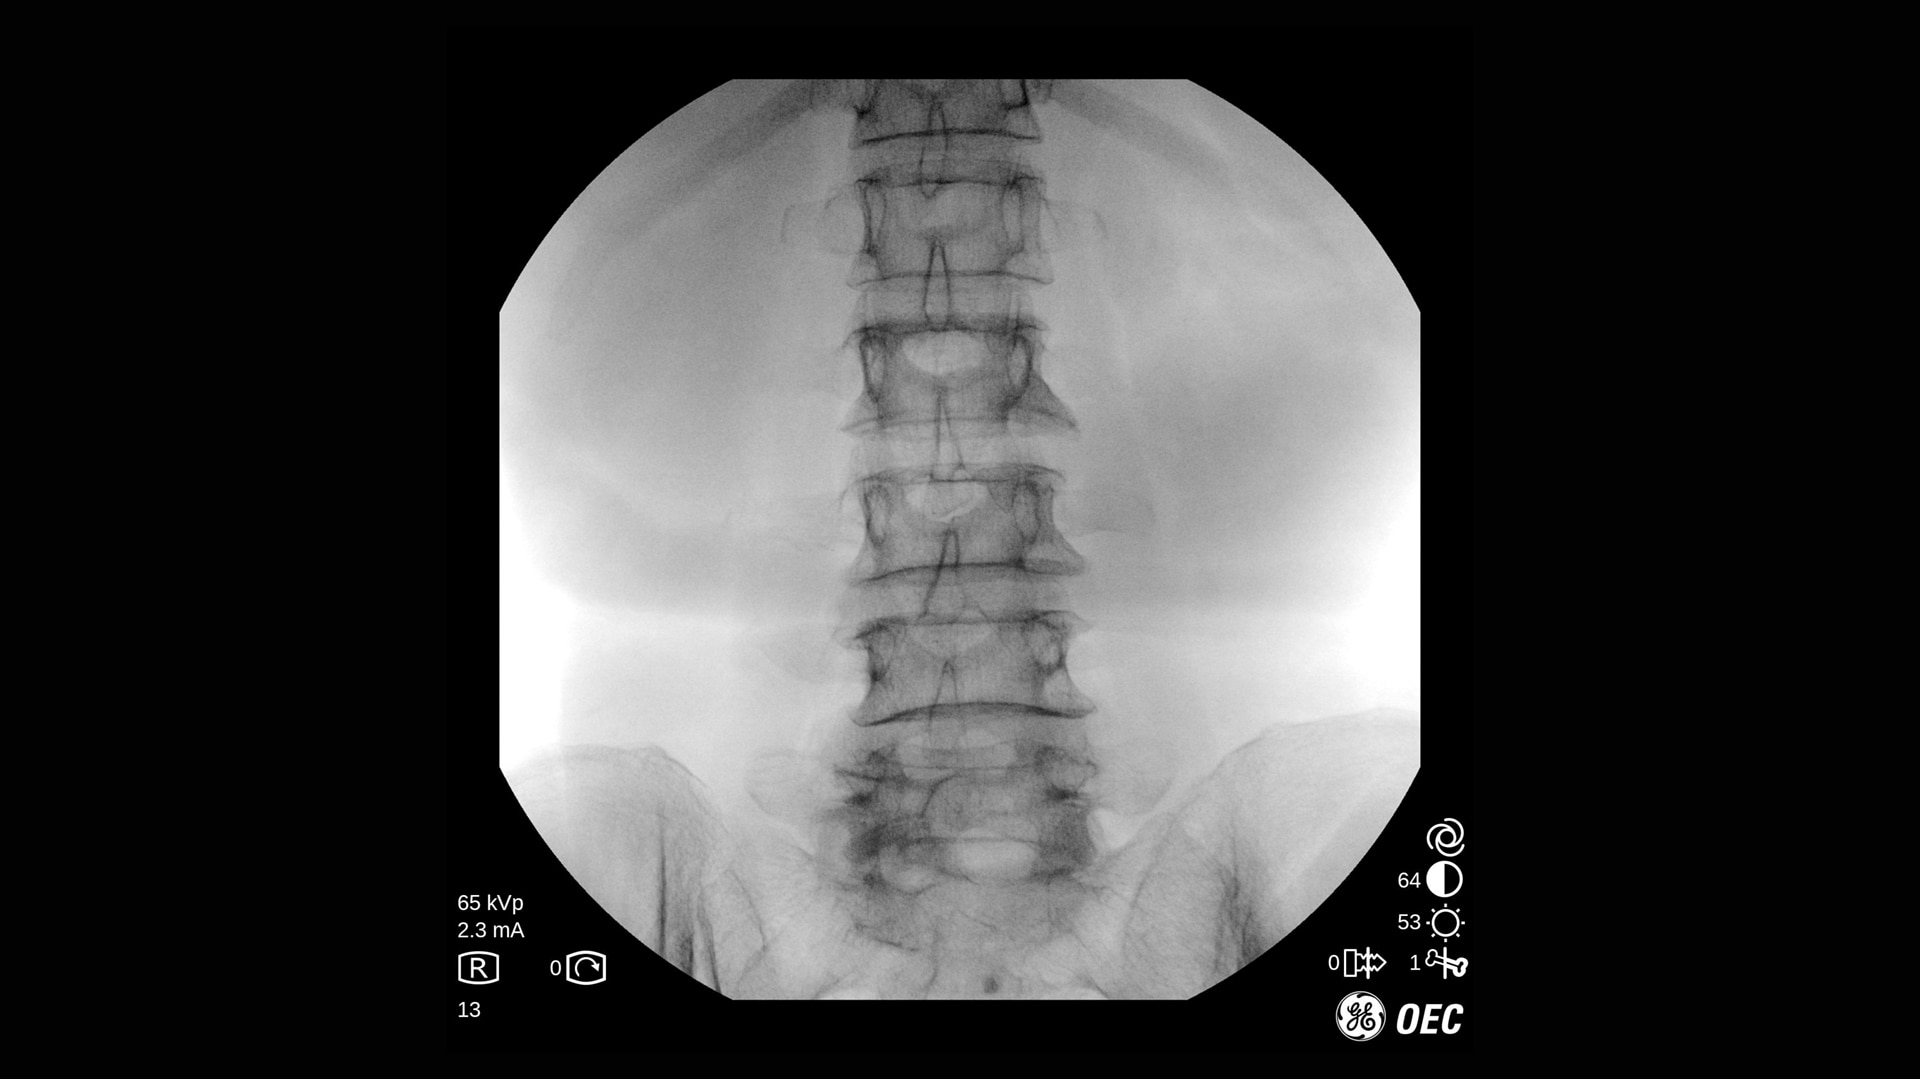

Der OEC One CFD unterstützt ein breites Spektrum klinischer Anwendungen: von endoskopischen Interventionen und Schmerztherapie bis hin zu komplexen Wirbelsäulen- und orthopädischen Verfahren.

Die Bildqualität ist bei verschiedenen Verfahren und Verfahrenseinstellungen essenziell, besonders auf engem Raum. Mit OEC One CFD erleben Sie die Bildqualität, die sie von den OEC mobilen C-Bögen erwarten, sowie die klinische Vielseitigkeit, die bei einem mobilen All-in-One-C-Bogen mit zwei Detektorgrößen benötigt wird.

Klarer Überblick über die Anatomie

Der OEC One CFD liefert gestochen scharfe Bilddetails – erfasst mit einem Flat-Panel-Detektor und dargestellt auf einem 27" 4K-UHD-Monitor direkt am OP-Feld.

Optimieren Sie Bildqualität und Dosis mit Live-Zoom, Adaptive Dynamic Range Optimization (ADRO), Bewegungsartefakt-Unterdrückung und weiteren intelligenten Bildverarbeitungsfunktionen.